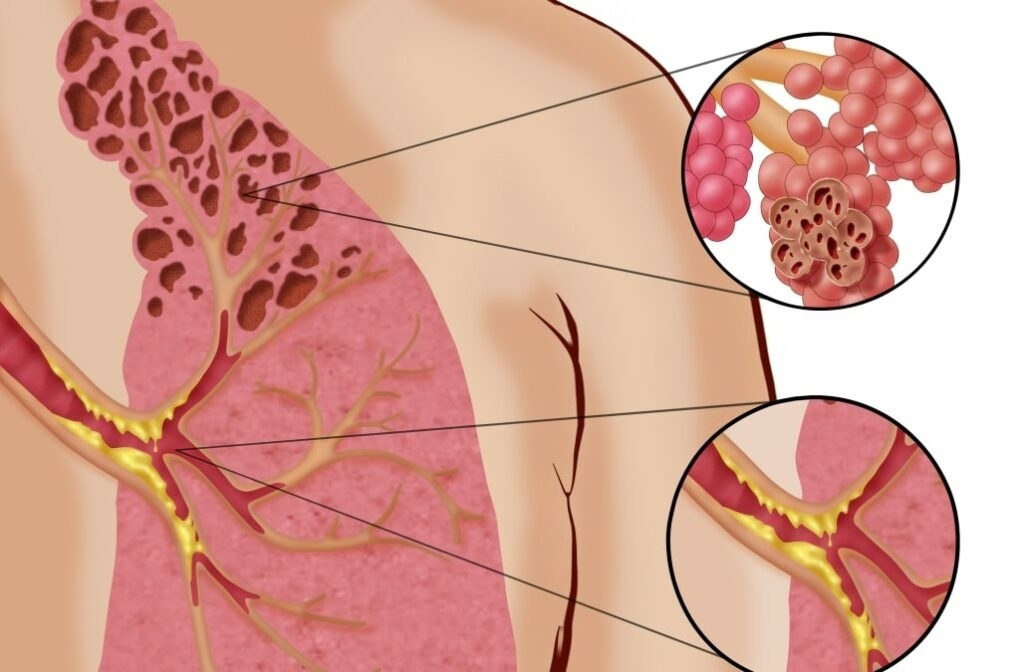

В России растёт число случаев «попкорновой болезни» среди вейперов — за последний год заболеваемость увеличилась на 30%.

Большинство заболевших — подростки и молодые люди до 35 лет. Наиболее распространённые диагнозы — EVALI и облитерирующий бронхит.

Симптомы включают лёгкий кашель, одышку и повышение температуры, а в тяжёлых случаях может развиться дыхательная недостаточность.

Были зафиксированы случаи, когда использование электронных сигарет приводило к необходимости реанимации.

22-летней девушке из Великобритании диагностировали рак лёгких в третьей стадии. Она курила вейпы в течение 7 лет, и теперь ей осталось жить всего 18 месяцев.

С 15 лет Кейли Боде почти не расставалась с электронной сигаретой, выкуривая по 600 затяжек в неделю. В январе 2025 года у неё появился кашель с коричневой мокротой и странными зернистыми частицами.

Медики были шокированы состоянием её лёгких, которое напоминало лёгкие 80-летнего человека. Врачи дали ей всего 18 месяцев жизни, а сама Кейли уверена, что причиной её болезни стали именно электронные сигареты.